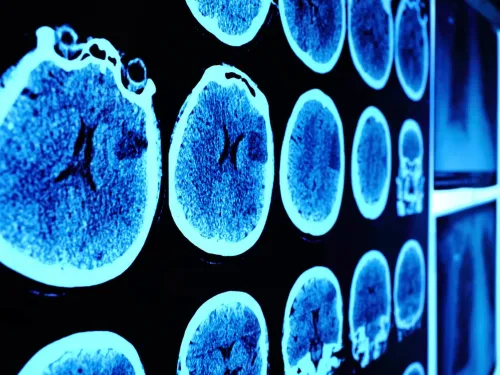

Diagnosis

Diagnosis means finding out whether you have cancer and, if so, what type of cancer you have. Doctors will do this by assessing you, and your symptoms, and by doing tests.